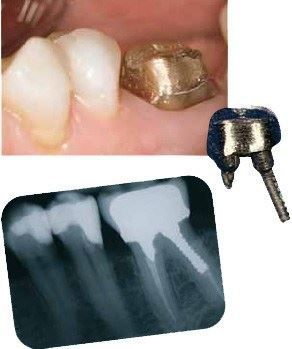

Hvis du har en defekt tand, som det ikke længere er forsvarligt eller muligt at reparere med en fyldning, så det kan holde, er det nødvendigt med en krone. Den vil gøre tanden mere holdbar og skal sikre, at tanden ikke knækker, så du derved risikerer

at miste tanden.

Denne tand kan ikke repareres med en fyldning, en krone er nødvendig.

Sådan ser tanden ud, efter at den er slebet til.

Tanden – nu med en guldkrone på

Er din tand rodbehandlet, og mangler der meget af den, er det ikke muligt at få en krone til at sidde fast. Så kan det være nødvendigt først at lave en opbygning, der sidder fast i roden med en stift.

Kronen kan så sidde fast på opbygningen.

Tanden har fået en guldopbygning. Nu er tanden blevet så stærk, at den kan bære en krone.